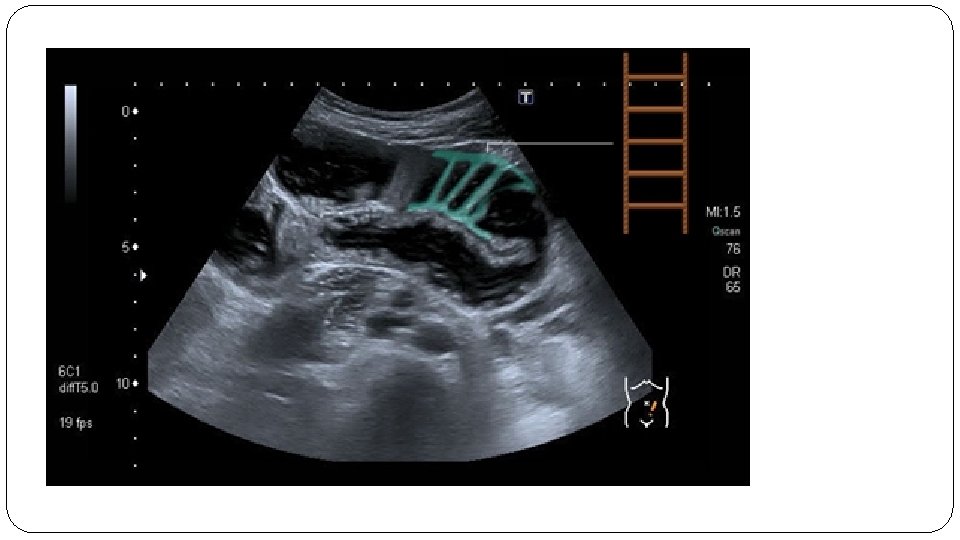

Ultrasound